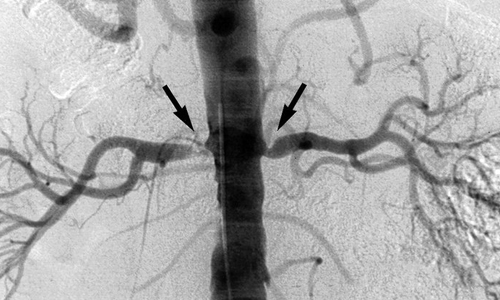

Прежде чем начать лечение, необходимо подтвердить диагноз. Для этого пациенту необходимо сделать УЗИ, КТ, МРТ, ангиографию с контрастом и визуализацию сосудов. Дополнительно измеряют силу кровотока.

Чтобы определить уровень поражения почек, нужно сделать клинические анализы. По уровню креатинина в крови врач определяет степень тяжести почечной недостаточности (если таковая присутствует). Это необходимо сделать перед ангиографией, поскольку пациентам с тяжелой почечной недостаточностью данное исследование противопоказано, их почки просто не смогут вывести контраст. Между тем, именно ангиография позволяет выявить причину болезни.